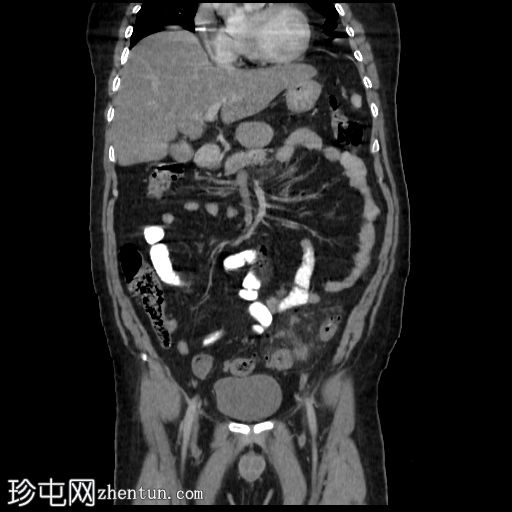

轴位

平扫

降结肠和乙状结肠可见多个小憩室,伴有少量小(亚厘米级)区域淋巴结肿大。周围脂肪和肠壁无明显增厚。

远端降结肠后壁可见一小(<15 mm)、局限性空腔,内含气泡,伴有不规则肠壁强化和轻度邻近肠系膜脂肪条索状改变。

未见脓肿、腹水、弥漫性气腹,提示IA期复杂性急性穿孔性憩室炎(局部穿孔)。

轻度脂肪肝。